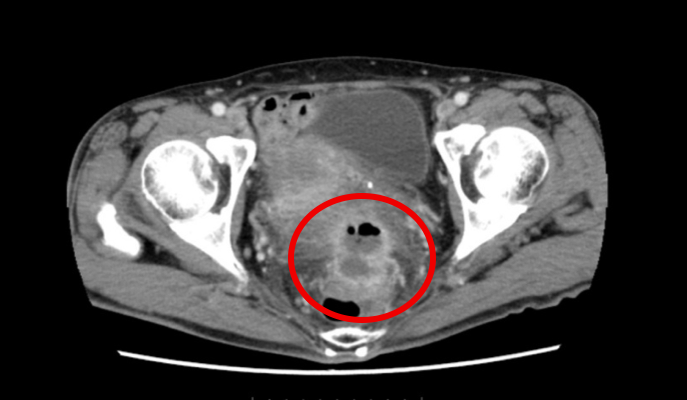

別の高さの画像を見ると、白い壁に囲まれた膿のたまりが確認できます。ちょうど子宮、S状結腸、直腸という臓器に囲まれています。

正面から見ても同じような膿のたまりが確認できます。